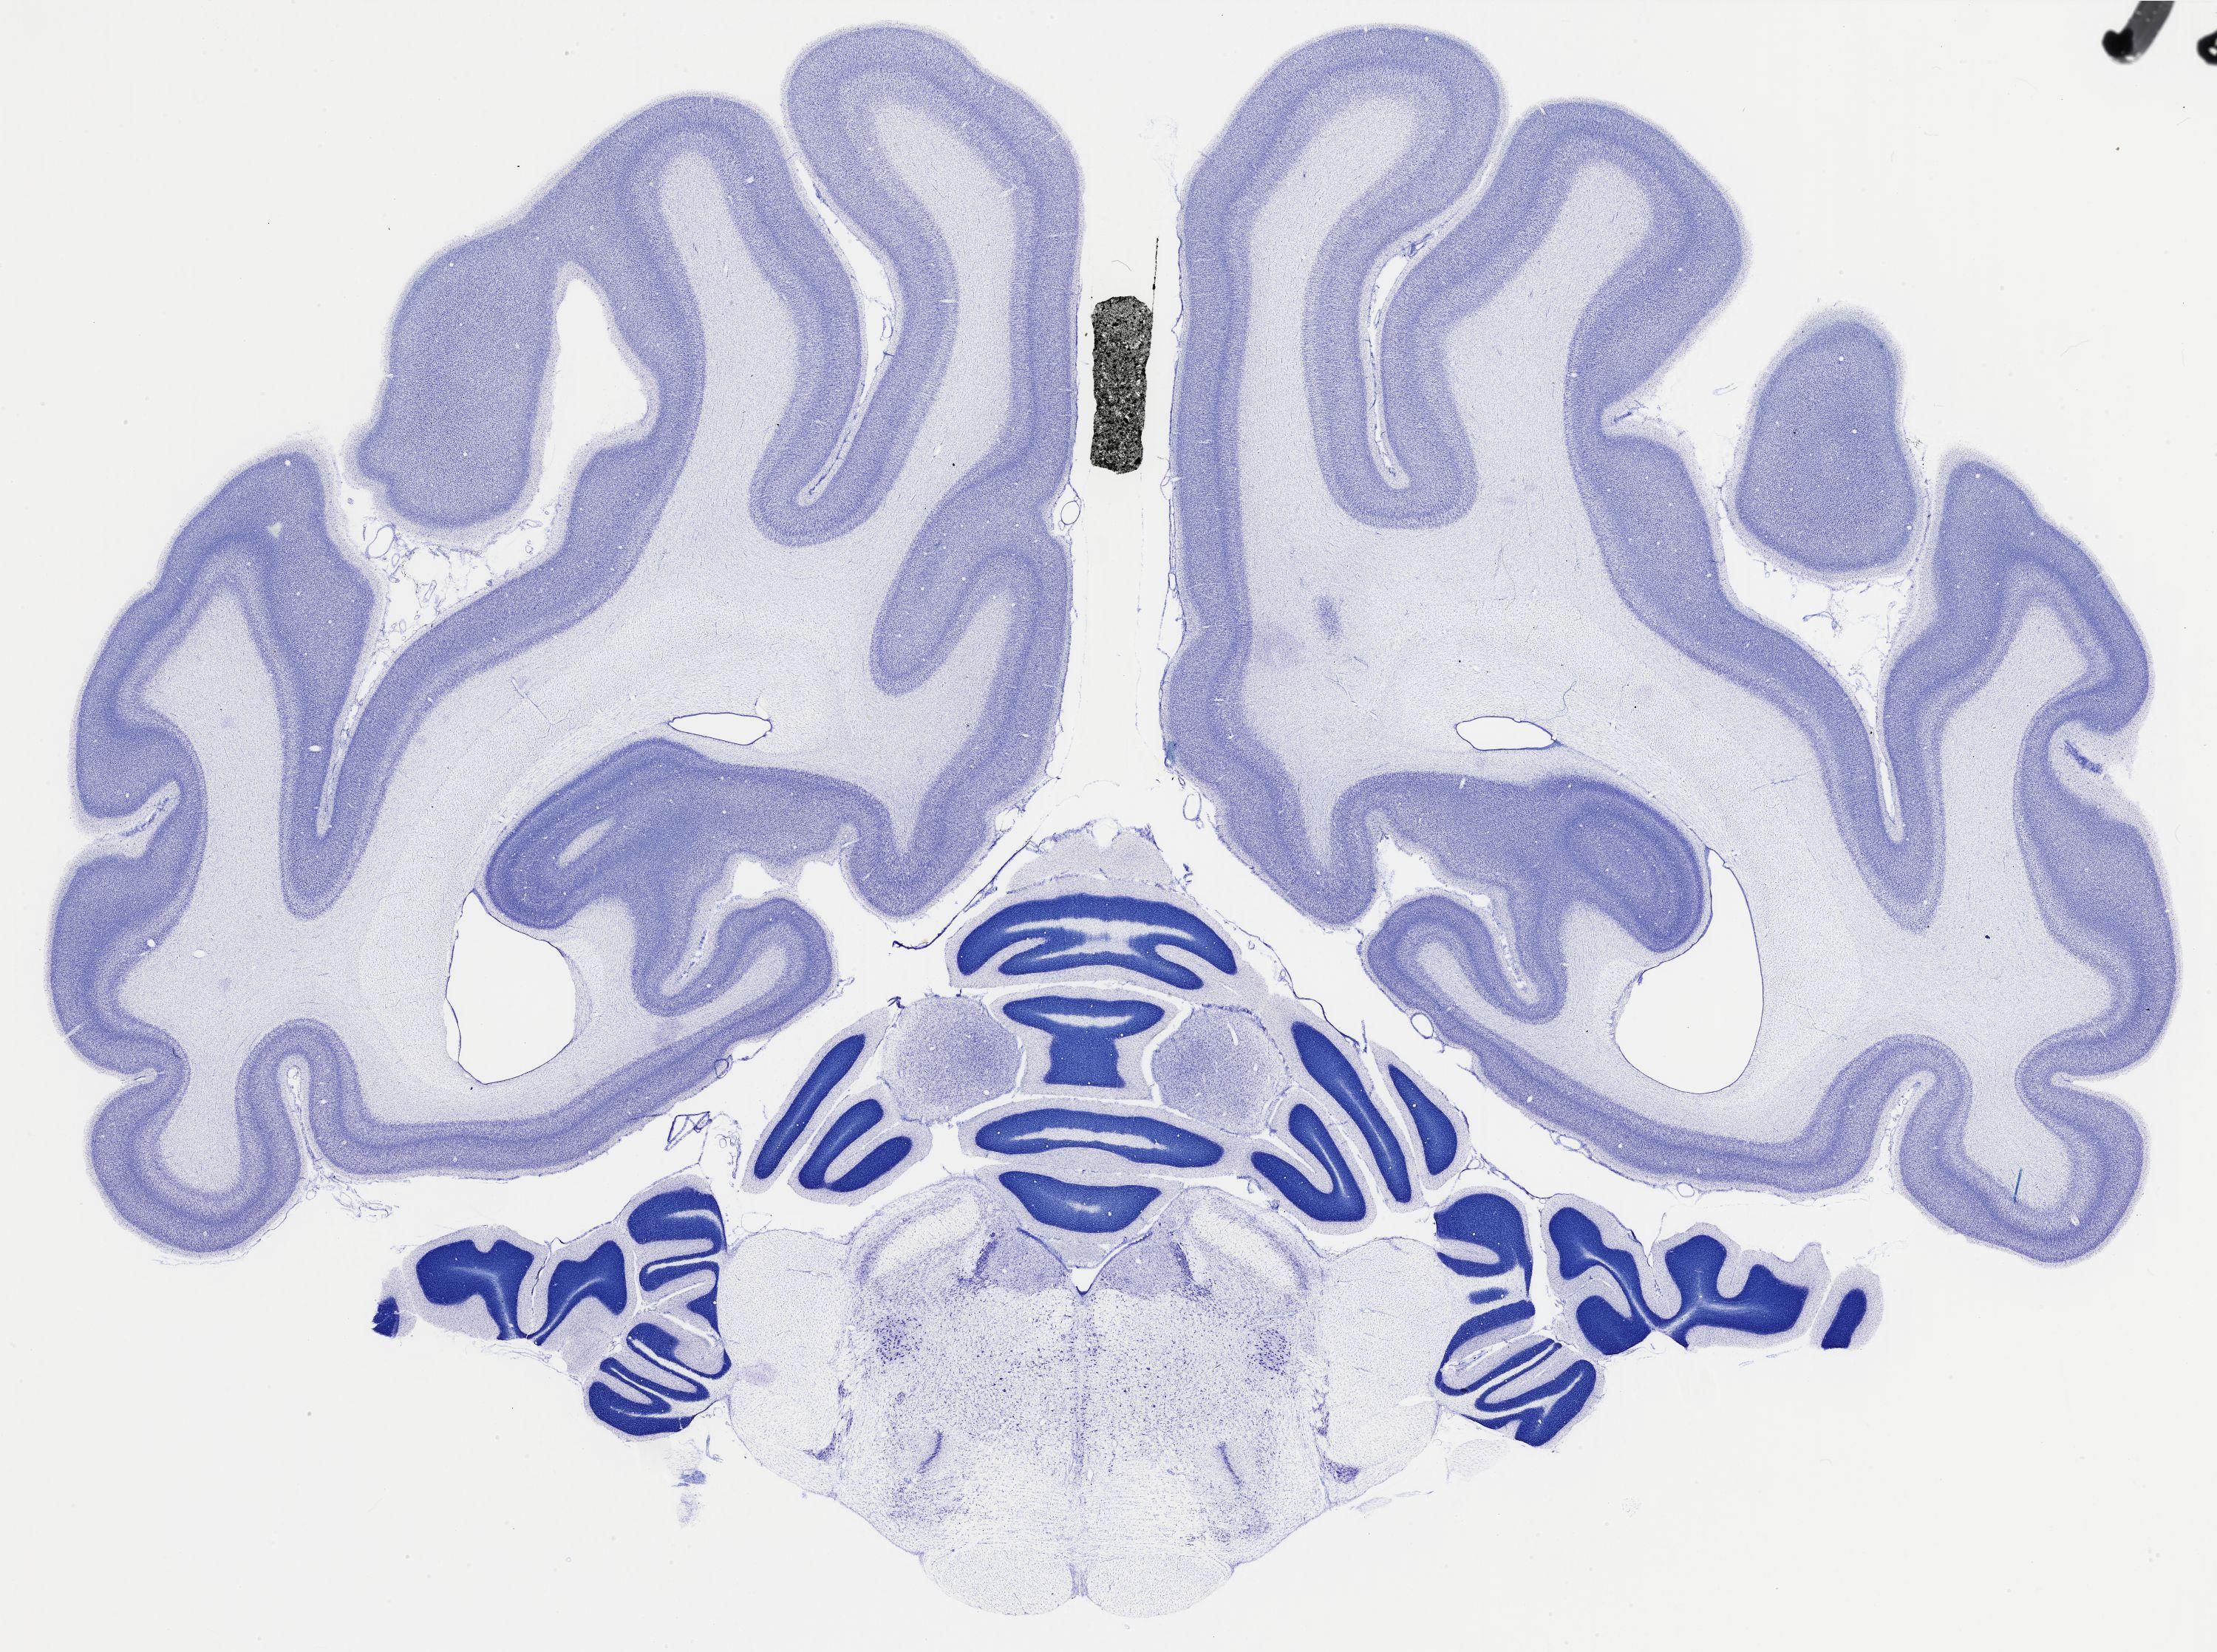

Datasets -> Chlorocebus Aethiops -> Nissl, coronal, histo, Whole-Brain, adult

[ Metadata ]   ·   Source: NeuroScience Associates

thumbnail

521